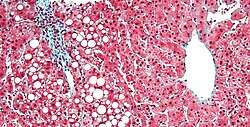

- Hepatic steatosis